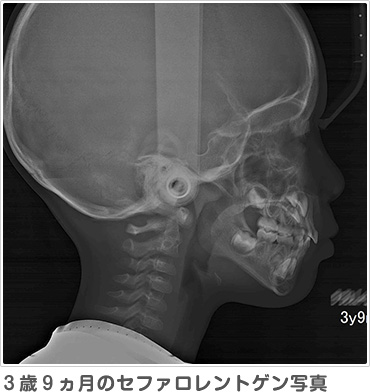

レントゲンは通常大きなレントゲンを2枚撮影します。パノラマレントゲンからは、おもに将来の永久歯の数が足りているか、永久歯の前歯はどのような形で生えてくるか、スペース不足はどのくらいか、などを予測します。セファロレントゲンからは、顔に対してアゴや歯並びがどのくらいの位置にあるのか、将来どのように成長する傾向があるのか、などを基準となる位置の角度を測って計測します。